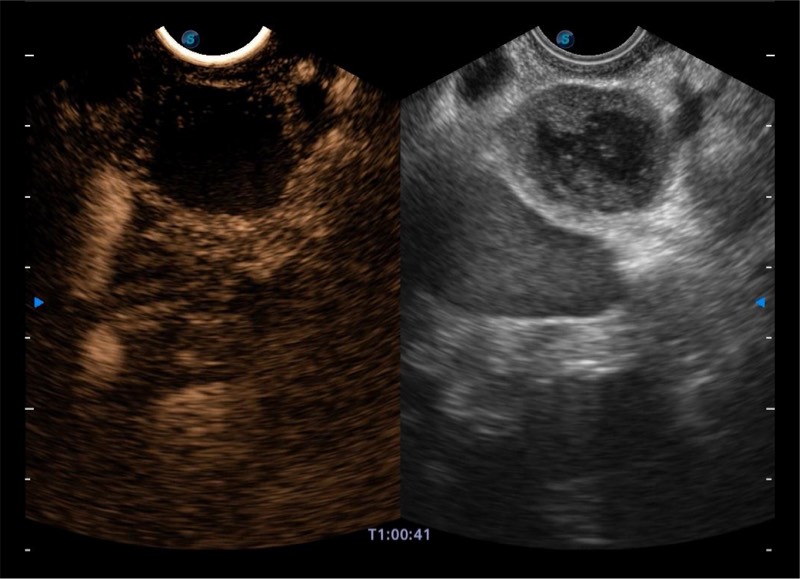

基于二十年的超声技术积累,竞技宝(JJB)官方网站提供了最新一代的独立超声主机,在提供高质量图像的同时满足多学科使用。具备常见多普勒技术并提供弹性成像、声学造影等高端影像技术。新一代传感器具有更强的抗干扰能力并减少图像伪影。